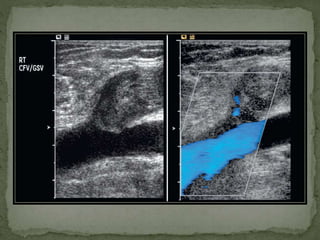

 Deep Venous System-

Evaluation of lower limb venous system is typically

directed towards deep system.

*Above knee , all deep veins lie medial to their

respective arteries.

Common fv – profunda f – (superficial) femoral v.